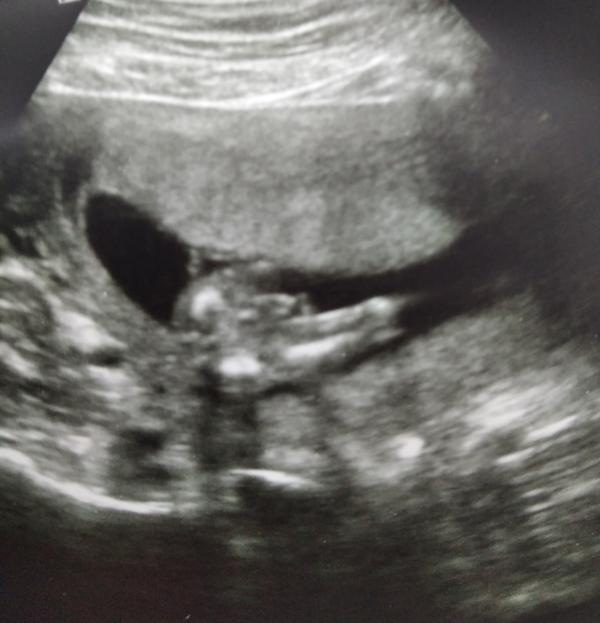

post image 1

Есиь специалисты УЗИ? мальчик или девочка?врач сначала сказала девочка,потом сказала все таки мальчик.срок 15 недель